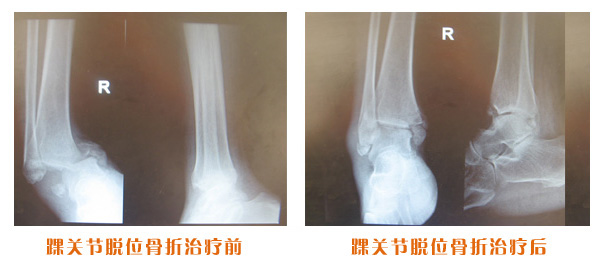

尺橈骨骨折治療前后